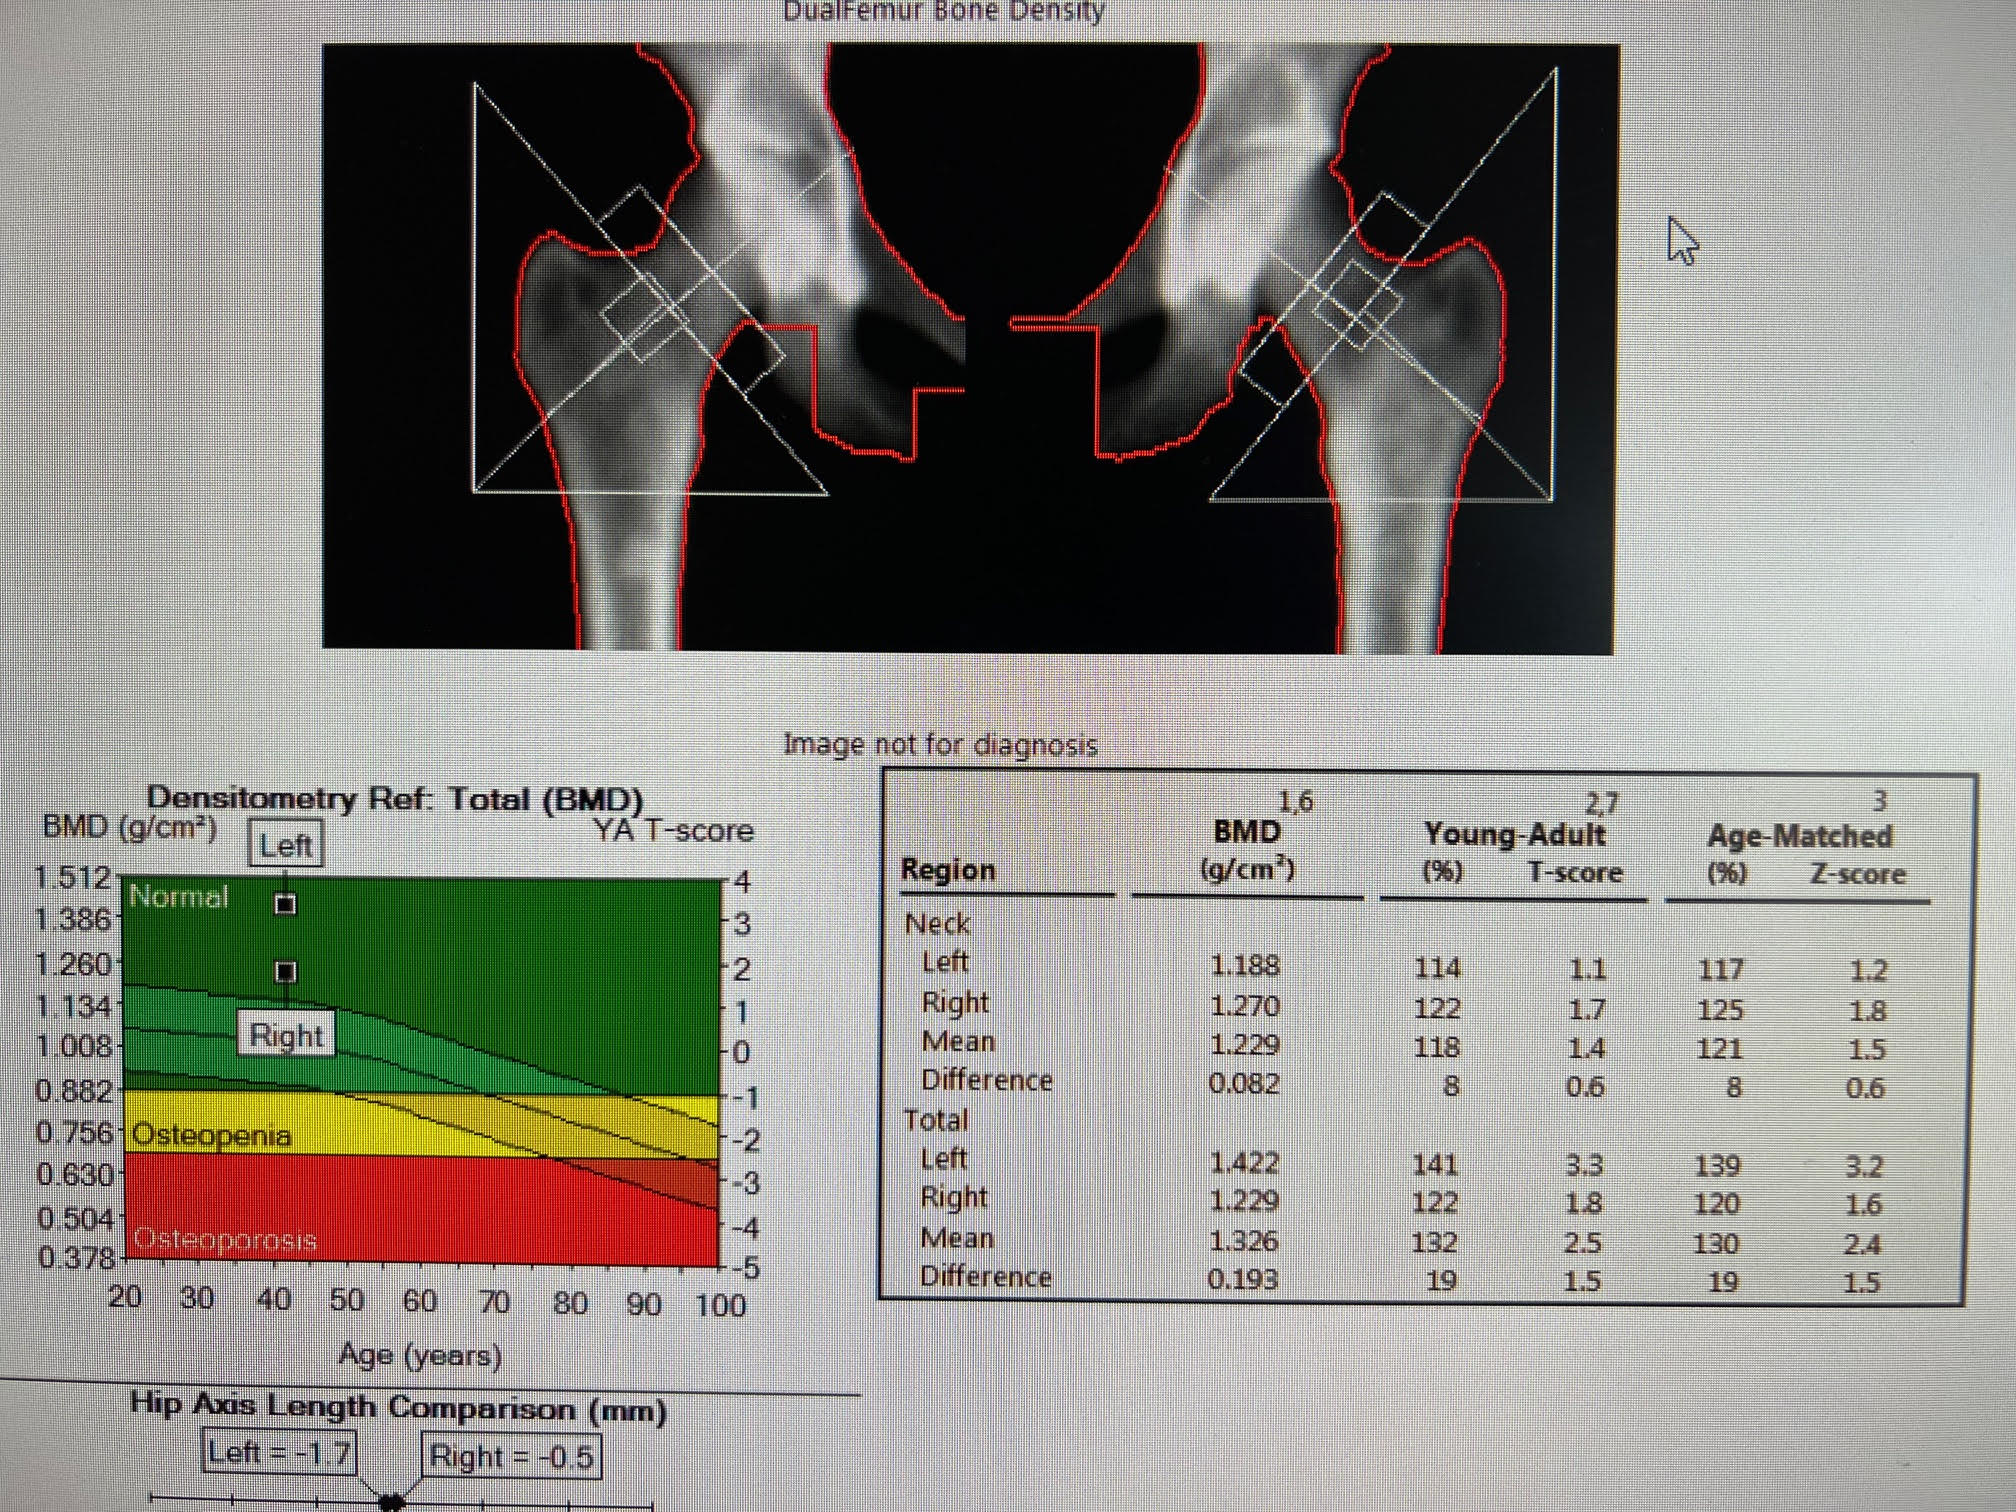

Increase in bone density at the left total hip with Z-score of 3.2